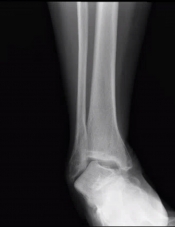

What’s the diagnosis? Gepost op 4 juni 20204 juni 2020 door netwerkvsseh What’s the diagnosis? @emdaily.cooperhealth.org Dit delen: Delen op X (Opent in een nieuw venster) X Share op Facebook (Opent in een nieuw venster) Facebook Delen op LinkedIn (Opent in een nieuw venster) LinkedIn E-mail een link naar een vriend (Opent in een nieuw venster) E-mail Afdrukken (Opent in een nieuw venster) Print Vind-ik-leuk Aan het laden... Gerelateerd